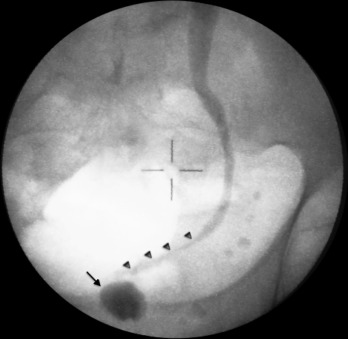

Foi realizada injeção de contraste pela nefrostomia (fig. 1 ) que mostrou estenose grave do ureter terminal (setas pequenas), bem como bexiga de muito baixa capacidade (seta).

Figura 1.

Pré‐operatório: bexiga de baixa capacidade (seta) e estenose do ureter terminal (setas pequenas) após injeção de contraste pelo cateter de nefrostomia.